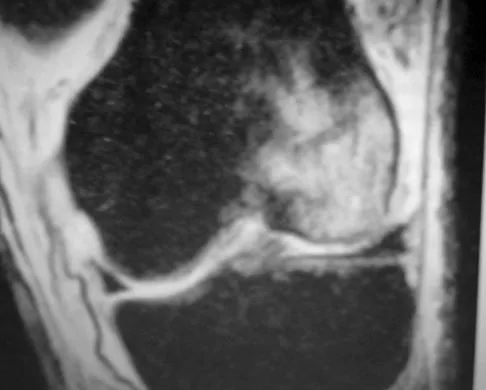

Question 18

A 28-year-old man has left knee pain after a snow skiing accident. The MRI scan shown in Figure 47 reveals which of the following?

Explanation